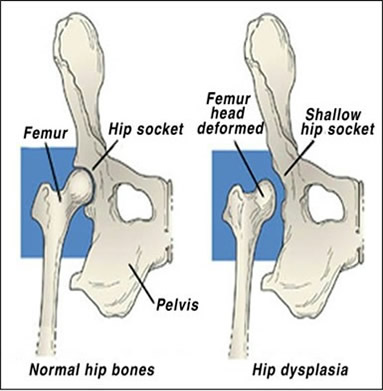

If a dog is known to be Hip Dysplastic it is imperative that they be spay / neutered so as not to pass on this negative genetic trait. Responsible breeding has the greatest impact on the prevalence of this disease. Along with not breeding a known Hip Dysplastic dog, breeders should also limit their levels of inbreeding. The greater level of genetic diversity any species has, the healthier that species is. Lack of genetic diversity is why many species have been placed on the endangered species list and in many cases have become or do become extinct. Hip Dysplasia can severely effect some dogs’ qualities of life and not even show to be positive in review of their x-rays. Others may appear to have severe Hip Dysplasia on their x-rays but exhibit little or no symptoms. In other cases a dog may be a simple carrier of the Hip Dysplasia gene yet it may never develop into the disease. If two such carriers breed, the potential for the disease actively developing in the offspring is significantly increased. Because inbreeding brings out the most recessive genetic traits it is easy to see how such practice can increase the odds of offspring developing the disease from seemingly healthy adults. It is important to realize that if a dog is diagnosed with the disease the effects of the disease can be minimized through dietary control and exercise. Probably the best known exercise is swimming. This disease when mild may also be treated with various over the counter aspirin medications (NOT TYLENOL – especially in cats where it can cause methemoglobinemia). When necessary, prescription medications can be used to manage the negative effects of Hip Dysplasia. Some cases, however, must be surgically repaired. When this is the case there are three primary options:

It is important that if this disease is suspected in any way that proper diagnosis be made. If positive, one should take the time to sit down with their veterinarian and discuss treatment options thoroughly. It is always a good idea to confirm the diagnosis through an unbiased second opinion by another vet. Treat your pet’s medical health the same as you would your own and get second and even third opinions if necessary. Your pet may survive a botched job from an unscrupulous vet, but at the same time their quality of life can be severely diminished if you are not careful.

Distemper, which was first discovered in the early 1900’s, is a very infectious disease that causes death in 50% - 80% of all dogs that are infected. The younger the dog, the greater the chance of death. Hip Dysplasia is a debilitating disease that is similar in nature to human arthritis. This disease tends to be primarily genetic in nature and affects mostly large breeds of dogs. Although other animals besides dogs can also have this disease.

Hip Dysplasia is a debilitating disease that is similar in nature to human arthritis. This disease tends to be primarily genetic in nature and affects mostly large breeds of dogs. Although other animals besides dogs can also have this disease.